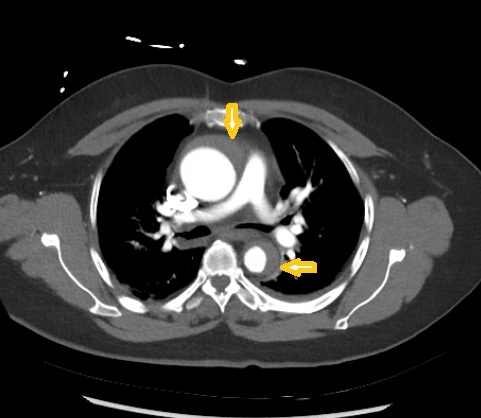

Given persistent suspicion for acute aortic syndrome, a dedicated CT angiogram of the aorta was performed, revealing an extensive intramural hematoma involving the aortic root, ascending aorta, arch, descending aorta, and abdominal aorta above the renal arteries.

An esmolol infusion was initiated, and cardiothoracic surgery was urgently consulted. Imaging was interpreted as most consistent with a penetrating aortic ulcer and sub-adventitial hematoma. The patient underwent emergent surgical replacement of the ascending aorta and hemiarch. Intraoperative transesophageal echocardiogram did not reveal aortic regurgitation or pericardial effusion.